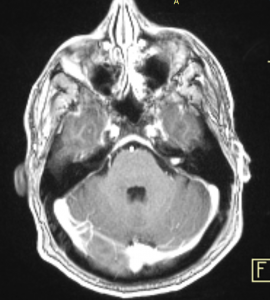

Ενδοκαναλικό Ακουστικό Νευρίνωμα αριστερά